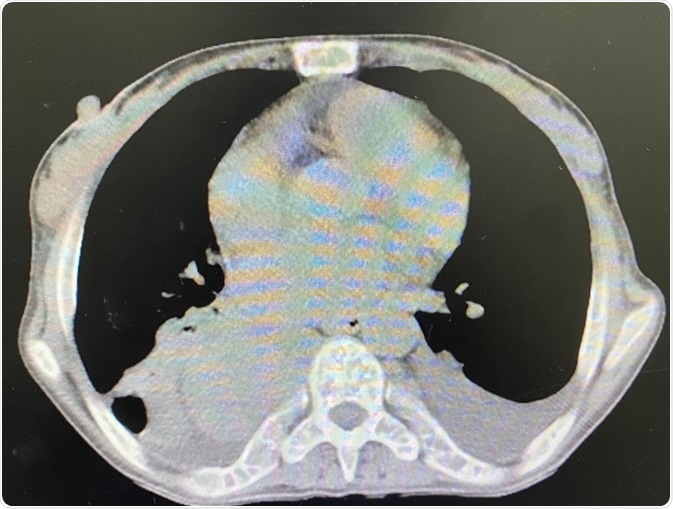

Image Credit: P.VARISA/Shutterstock.com

Controlling the infectious source and tissue debridement (when necessary) are two fundamental steps in the surgical treatment of mediastinitis. The strategy is decided according to the underlying cause and magnitude of the disease. This is usually established with the use of imaging techniques, more specifically cross-sectional imaging studies.